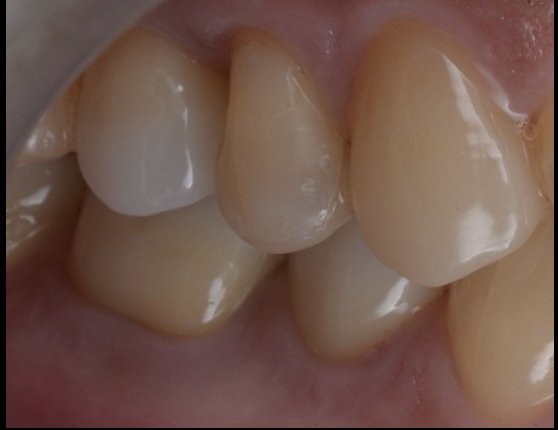

今回の症例も、外科処置を行わずに、歯肉が自然に健康的なラインへ整いました。

その結果、

治療後には歯肉の炎症も消失し、自然な歯肉形態が獲得できました。

治療終了後は以下の改善が得られました。

- 歯肉が健康的なラインに安定

- セラミッククラウンが自然に適合

- 咬合が安定し、日常生活の痛みが消失

- 外科なしで歯を残すことに成功